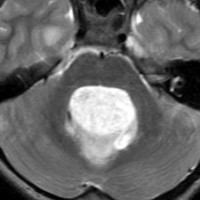

毛様細胞性星細胞腫 pilocytic astrocytoma

毛様細胞性星細胞腫です。左のガドリニウム増強T1像では髄芽腫と区別できませんが,真ん中のCISSの画像で低信号,右のT2強調画像で強い高信号になるのが特徴です。最上部に小さなのう胞が2つあります。